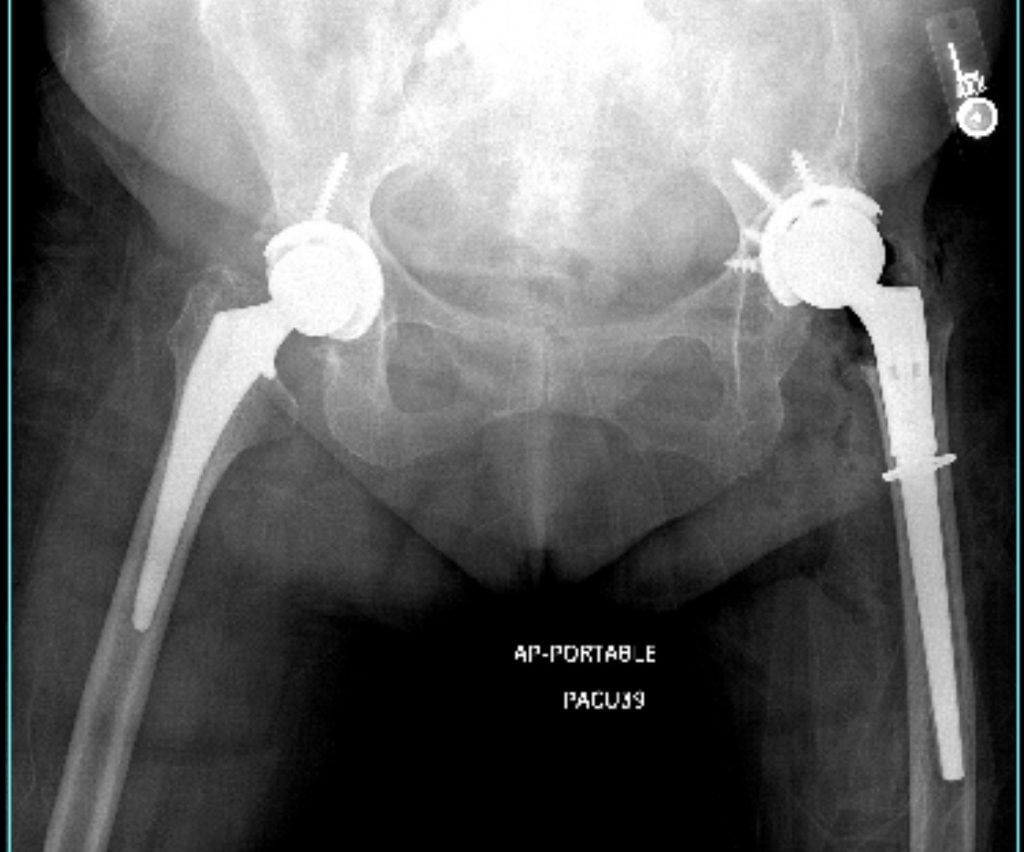

She has also replaced both of my hips, including a very complex revision of a Smith-Petersen hip procedure originally performed in 1960. For each surgery, Dr. Gausden explained the procedure thoroughly and ensured I felt fully informed. I experienced no bleeding, no bruising (except in the extremely complex left hip revision), minimal pain, and no complications from any of my procedures.